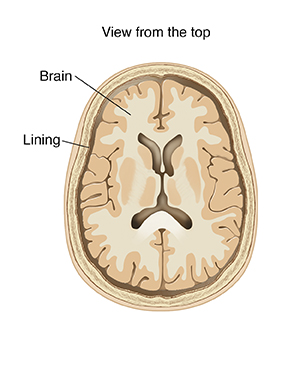

Meningitis is an infection or inflammation of the membrane and fluid around the brain and spinal cord. Viral meningitis is caused by a virus. It may start as another illness, such as the stomach flu. It most often happens in children younger than 5 years of age. It's not the same as bacterial meningitis, which is a serious illness caused by bacteria. Bacterial meningitis needs to be treated with antibiotics right away. Viral meningitis is often mild and less serious, except in infants younger than 3 months and with certain viruses such as herpes simplex. It will go away with no treatment.